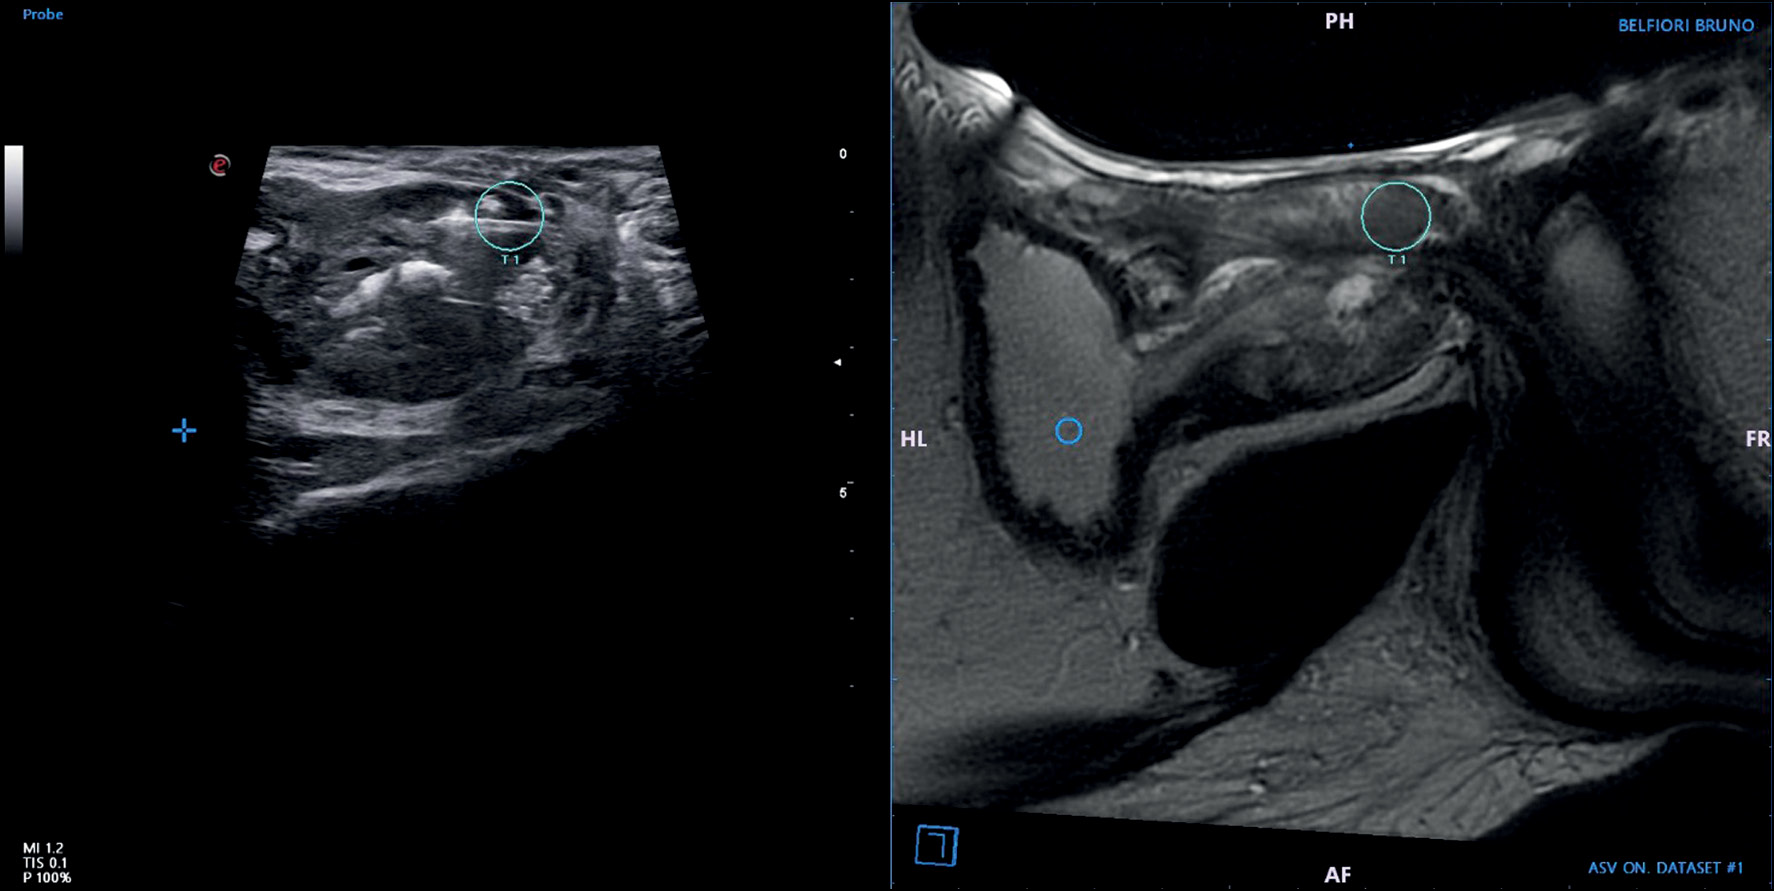

In this method, the operator images the prostate using US, as has been used for decades. While viewing the prostate, the MR images of that prostate, in which imaging was performed beforehand and images were stored in the device, are fused with real-time US images using a digital overlay, allowing the target(s) previously delineated by a radiologist to be brought into the US machine’s aiming mechanism. Fusion produces a three-dimensional (3D) reconstruction of the prostate, and the aiming and tracking of biopsy sites occur on the reconstructed model (Fig. 1 and 2) [25]. Several commercial platforms are now available, each with a different method of coregistration and a different hardware platform for lining up the biopsy with the coregistered picture [3]. Compared with VE, MRI–TRUS fusion-guided biopsy may have higher reproducibility because of less operator dependence and delivery of real-time feedback on actual biopsied areas [3]. The disadvantages include higher software/device costs, dependence on software for accuracy, and the associated learning curve and operator training [26] (Fig. 3 and 4).

Fig. 2. MRI–TRUS fusion-guided prostate biopsy. The prostate and lesions identified on MR images (in this case, on T2W imaging) are segmented. During the procedure, a 2D TRUS scan of the prostate was performed. Images were recorded semiautomatically. Co-viewing images can be tiled or overlaid. By merging the two images, the urologist can locate the lesion during a biopsy using real-time ultrasound guidance.

Fig. 4. Magnetic resonance imaging is fused with real-time TRUS using a digital overlay, allowing the target(s) previously delineated by a radiologist to be brought into the ultrasound machine’s aiming mechanism. Fusion enables the reconstruction of the prostate, and the aiming and tracking of biopsy sites occur on the reconstructed model.